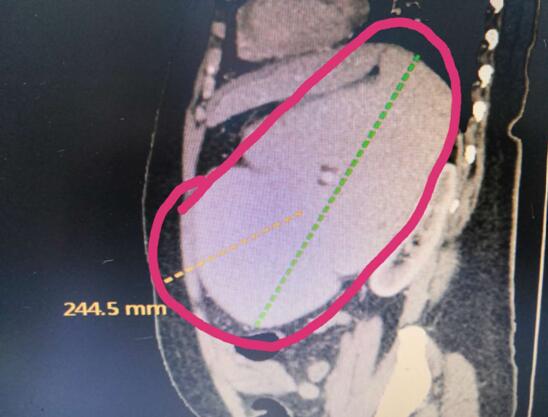

患者B,女,51歲,因牙齦出血1年入院,入院診斷為:乙肝,肝炎后肝硬化,門脈高壓癥,巨脾,脾亢,白細(xì)胞、血小板減少,中度貧血。5年前,曾在外院行介入脾栓塞術(shù),脾臟不僅沒有縮小,反而越來越大,脾下緣已經(jīng)超過腹部正中線、抵達(dá)臍部,就像幾個(gè)月“身孕”的婦女,給病人帶來巨大身心負(fù)擔(dān)。

(術(shù)前腹部CT顯示巨脾)